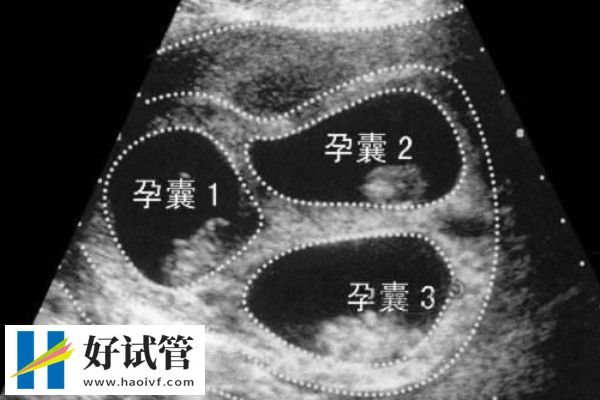

试管婴儿胚胎移植是将在实验室内进行体外授精后,在培养皿中培养形成的早期胚胎移植回准妈妈的子宫内,使早期胚胎可以在母体内继续生长发育的过程。

而目前该项目中有多余胚胎的情况下有两种选择,分别是攒胚胎和养囊,其中养囊的成功率会更高一些,因为囊胚的潜力更大,同时也更适合人体生理需求。

攒胚胎指将取卵后获得的胚胎通过冷冻技术保存起来,在适当的时候再进行移植。这包括玻璃化冷冻法和程序冷冻法,旨在保护胚胎的生命力,使其处于休眠状态。而养囊指将取卵后获得的胚胎继续培养至囊胚阶段,再进行移植。囊胚是胚胎进一步发育的产物,通常在卵子受精后的第五到七天形成。